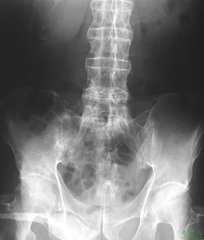

患有强直性脊柱炎,患者的脊柱关节会受到严重的影响,患病后,患者的关节活动严重受限,对患者的生活也造成了严重的影响。那对于强直性脊柱炎的治疗,我们大多数人都十分关注疗效的问题。

那么强直性脊柱炎要怎样治才效果好呢?